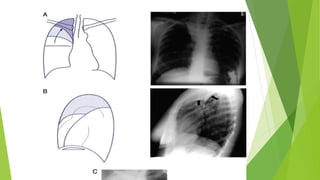

 The radiological signs of collapse will depend upon the aetiology, degree of

collapse, and associated consolidation or pleural pathology.

 Signs may be

#direct (related to loss of lung volume and collapsed

 lobes) or

#Indirect (occurring as result of compensatory changes due to volume loss),

leading to shift of the mediastinal structures

Direct signs

These include:

† Increased opacification in the area of atelectasis. Air bronchograms are

normally a feature of consolidation but may also b present in lobar collapse.

† Displacement of fissures. This occurs with large degree of collapse.

† Loss of aeration. If the collapsed lung is adjacent to the mediastinum or

diaphragm, then loss of definition of these structures indicates loss of

aeration (the silhouette sign).

† Vascular signs. In partial collapse, crowding of vessels may be

seen.

Note the loss of the right heart border silhouette

due to partial atelectasis of the RML

Crowding of vessels and

bronchi.